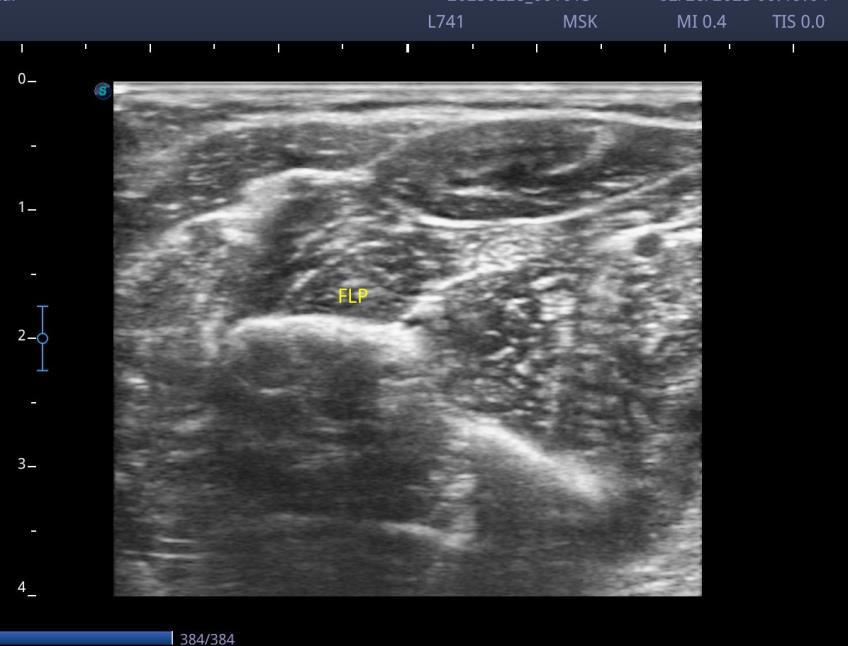

Case 2

Ultrasound-guided focal treatment with botulinum toxin in the upper limb

FLEXOR DIGITORUM SUPERFICIALIS, 40 UI

FLEXOR POLLICIS LONGUS, 30 UI